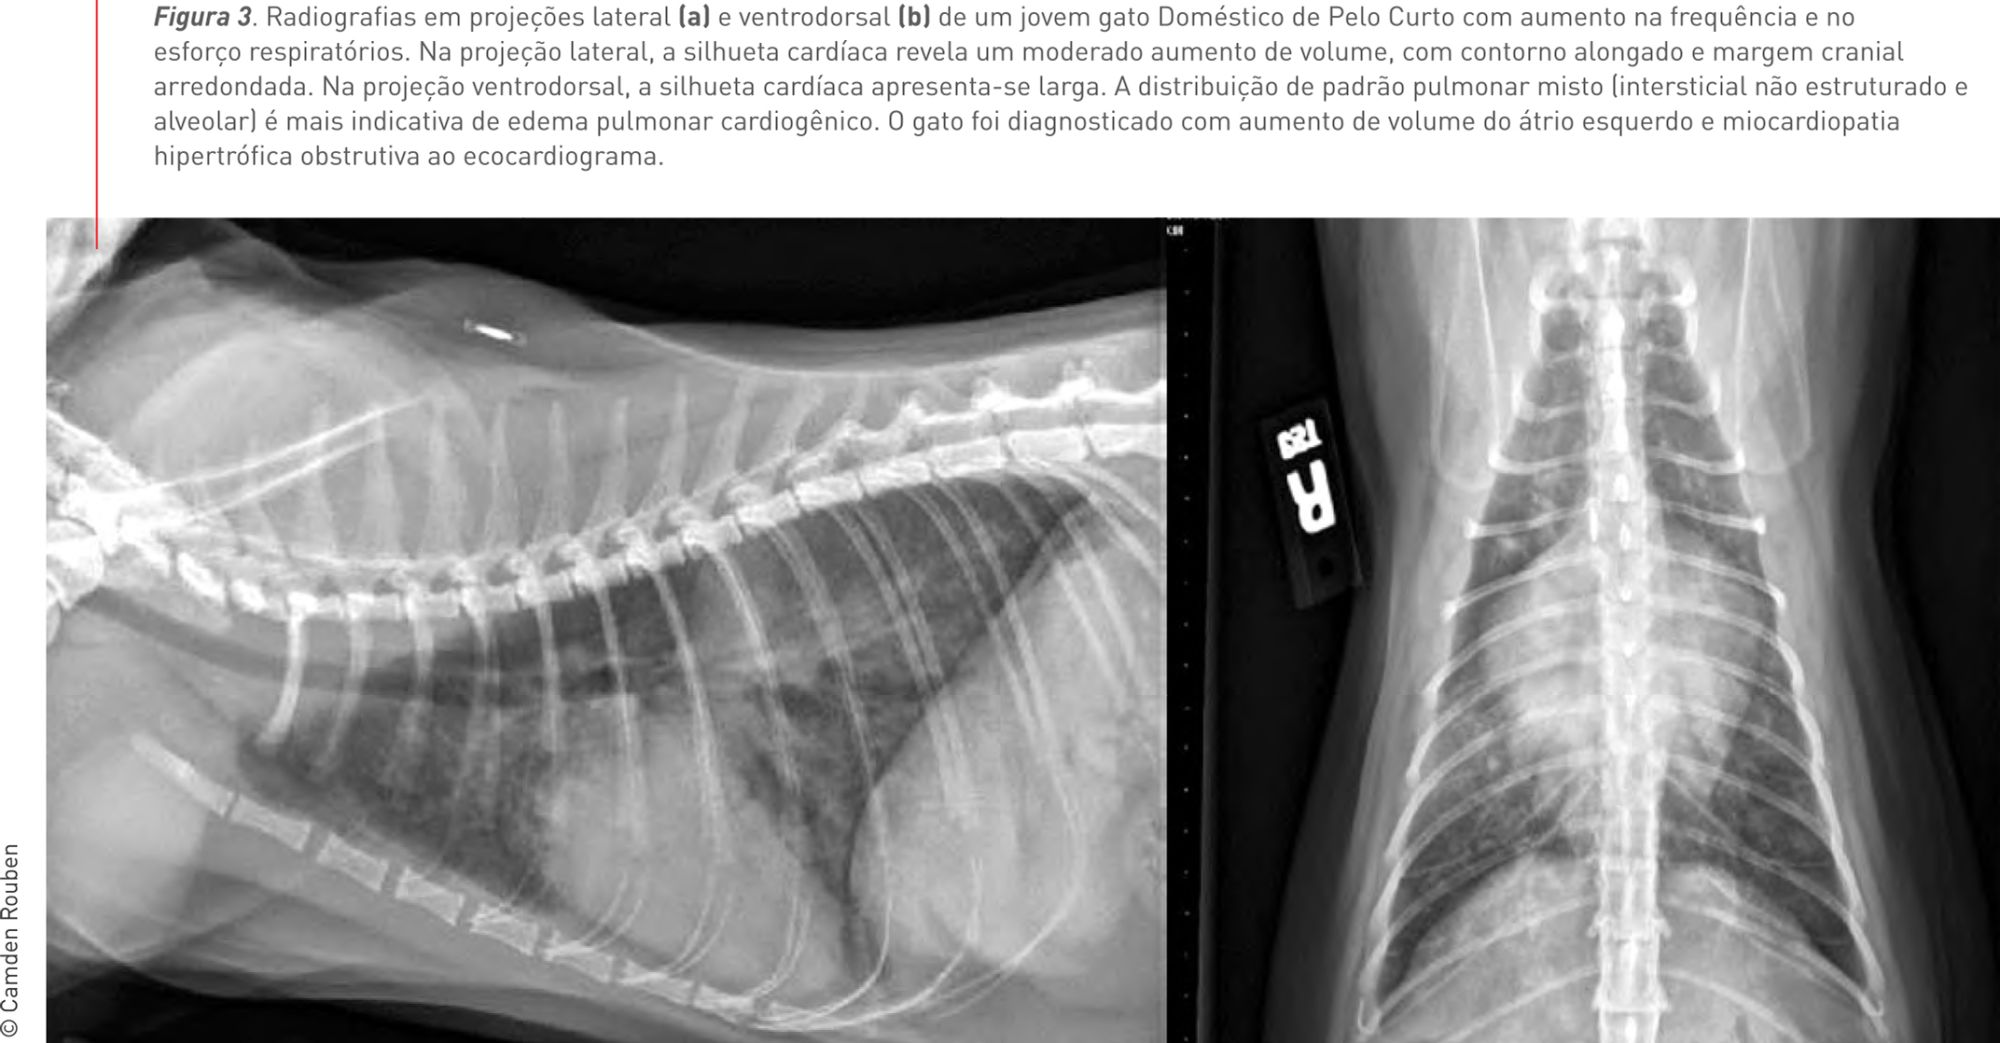

Figura 3. Radiografias em projeções lateral (a) e ventrodorsal (b) de um jovem gato